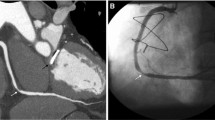

In comparison to coronary calcium scans, coronary CTA is an even more adept screening tool for CAD, given its ability to assess stenosis as well as myocardial disease and presence of infarction (Figs. 2 and 3). A 2009 comparison of coronary CTA to invasive coronary angiography showed sensitivity of 100%, specificity of 93%, positive predictive value (PPV) of 95%, negative predictive value (NPV) of 100%, and accuracy of 97% on a per-patient analysis in the general population for excluding CAD of greater than 50% luminal stenosis [11]. Other investigations by Pontone et al. and Maruyama et al. on coronary CTA in the general population have had comparable results [12, 13]. A fourth report did not complete a per-patient data analysis, but did describe similar sensitivity, specificity, accuracy, PPV, and NPV on a per-segment basis as 84.3%, 98.6%, 96.1%, 92.2%, and 96.9% [14]. With regard to the diagnostic performance and utility in patients with heart failure, a 2009 investigation concluded sensitivity of 100%, specificity of 96%, PPV of 0.9, and NPV 1.0 for > 50% luminal stenosis on a per-patient basis [15]. Papers by Andreini et al. (in 2007 and again in 2009), Ghostine et al., Polain De Warux et al., and Boulmier et al. have been published with concurrent results [16,17,18,19,20]. One possible complaint with these prior investigations is the relatively small patient population in the study. Yet, more recently, a larger (n = 537), multicentered prospective trial demonstrated that coronary CTA has sensitivity, specificity, NPV, and PPV of 92–100%, 83–93%, 88–100%, and 81–92%, respectively, for detection of > 50% luminal stenosis on per-patient model in the heart failure population [21].

In contrast to prior studies examining patients with heart failure only once stabilized, Srichai et al. showed that coronary CTA retained accuracy (96.7%), although sensitivity (62.5%) was decreased, in patients who are in acutely decompensated heart failure with average heart rate of 75 beats per minute [22]. These findings are supported by a separate report in the general population, which found no changes to diagnostic values across patients in three different heart rate groups [14]. Oncel et al. found that coronary CTA retained sensitivity (100%), but did have decreased specificity (88.9%) in patients with atrial fibrillation [23]. Follow-up papers in patient populations in Europe and China also showed high sensitivity (90–100%), with slightly decreased specificity (75–84%) for patients in atrial fibrillation [24,25,26]. In addition, coronary CTA is reliable in patients with known CAD and coronary artery stents, as well as patients with end-stage renal disease (Figs. 1 and 2) [27, 28]. In short, coronary CTA is a suitable tool for distinguishing ischemic from dilated cardiomyopathy in a large and diverse patient population.